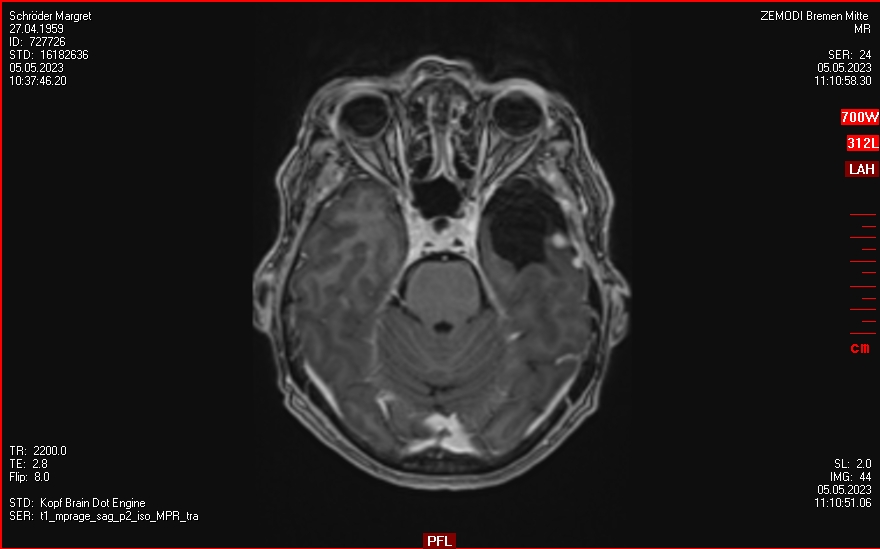

30.06.2025

Kontrolle bei Zemodi in Bremen

Nun scheint eines der Menigeome (links temporo-okzipital) gewachsen zu sein.

Auswertungen des MRTs wurden von Zemodi, eines Neurochirugen vom Klinikum Bremen-Mitte sowie von Prof. Lippitz gemacht.

• Die Tumorkonferenz im Klinikum Bremen-Mitte schlägt vor, mit Prof. Lippitz zu klären, ob er behandeln kann  und bietet die Resektion des betroffenen Tumors an.

• Prof. Lippitz empfieht ein erneutes MRT im August 2025, da das MRT nicht eindeutiges Wachstum zeigt.